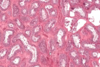

Endocrine pancreas cells

Pancreatic acini (with exocrine cells) - dark purple

Pancreatic islet (with endocfine cells) - light purple

Islet of Langerhans (endocrine pancreas), surrounded by serous acini (exocrine pancreas)

Assume that most cells in middle of islet are beta and cells at periphery of islet is alpha cells